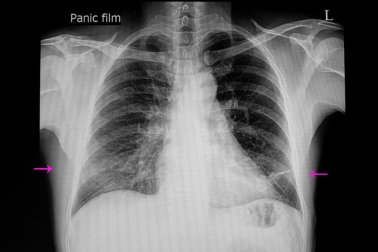

Um exame clínico e a realização de uma radiografia costumam ser suficientes para diagnosticar a atelectasia. Ainda assim, várias técnicas podem ser usadas para confirmar o diagnóstico ou medir a gravidade da doença.

Elas incluem tomografia computadorizada, broncoscopia, ultrassom e oximetria. De fato, a broncoscopia permite observar as obstruções e até eliminar o bloqueio.